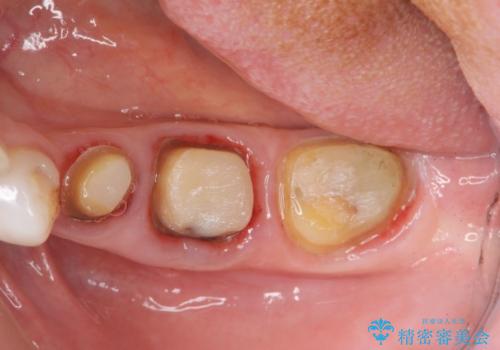

- 虫歯治療、老朽化した銀歯や詰め物 コンポジットレジンのやりかえを希望され来院されました。

クラウンやレジン下に再発していた虫歯を丁寧に除去したのち、歯ぐきの腫れが改善が見られないため歯周外科を行い歯ぐきの状態を整えたのちにジルコニアクラウンを製作していきます。